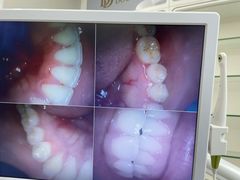

• 牙博士口腔品牌连锁(杨浦店)

• -牙博士口腔品牌连锁(杨浦店)

韩秀凤_2940 | 21-11-10

小明 | 21-11-08